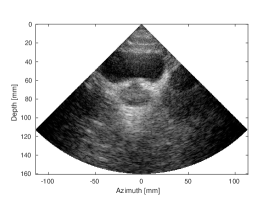

Qualitative evaluation for the phantom frame is presented in S along with quantitative measurements, provided in the supplementary materials. A magnified region depicts the response from one of the wires of the phantom. A thinner appearance, as compared to the apodized MLT image, can be observed for both and MLT frames processed with the proposed CNN, since no apodization was needed to attenuate the artifacts. Quantitatively, the CR of the anechoic cyst as compared to the nearby tissue, was restored for the case of MLT, whereas for the MLT case it was improved by almost dB as compared to the SLT. Since the network was trained on the data with a higher number of a strong reflectors, thus higher artifact content, it is possible that the artifact content is overestimated in some cases. The images of the bladder (S) appear to have a higher quality in the MLT and MLT CNN corrected cases, as compared to the respective apodized versions. Quantitatively, the improvement in contrast over apodized MLT was around dB for -MLT and dB for for MLT.

| (d) SLT | (e) MLT, (Tukey, =0.5) | (f) MLT, CNN | |

| CNR=1.41, CR=-27.37dB | CNR=1.19, CR=-12.99dB | CNR=1.41, CR=-25.96dB |